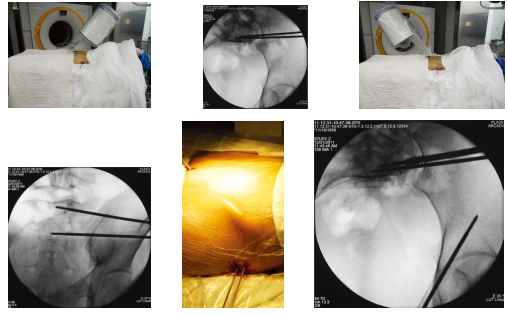

骨盆骨折的闭合复位经皮通道螺钉微创治疗技术

以下图片是我科骨盆骨折的闭合复位经皮通道螺钉微创治疗技术的一例患者资料

图:H术前透视标记

图:I、J、K、L、M、N、O、P、Q、R术中操作透视

图:S手术切口外观